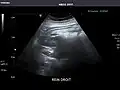

Left kidney -

Kidneys: Right and left kidneys measure 11.5 cm and 12 cm in length respectively. No hydronephrosis. Small left lower pole kidney cyst.